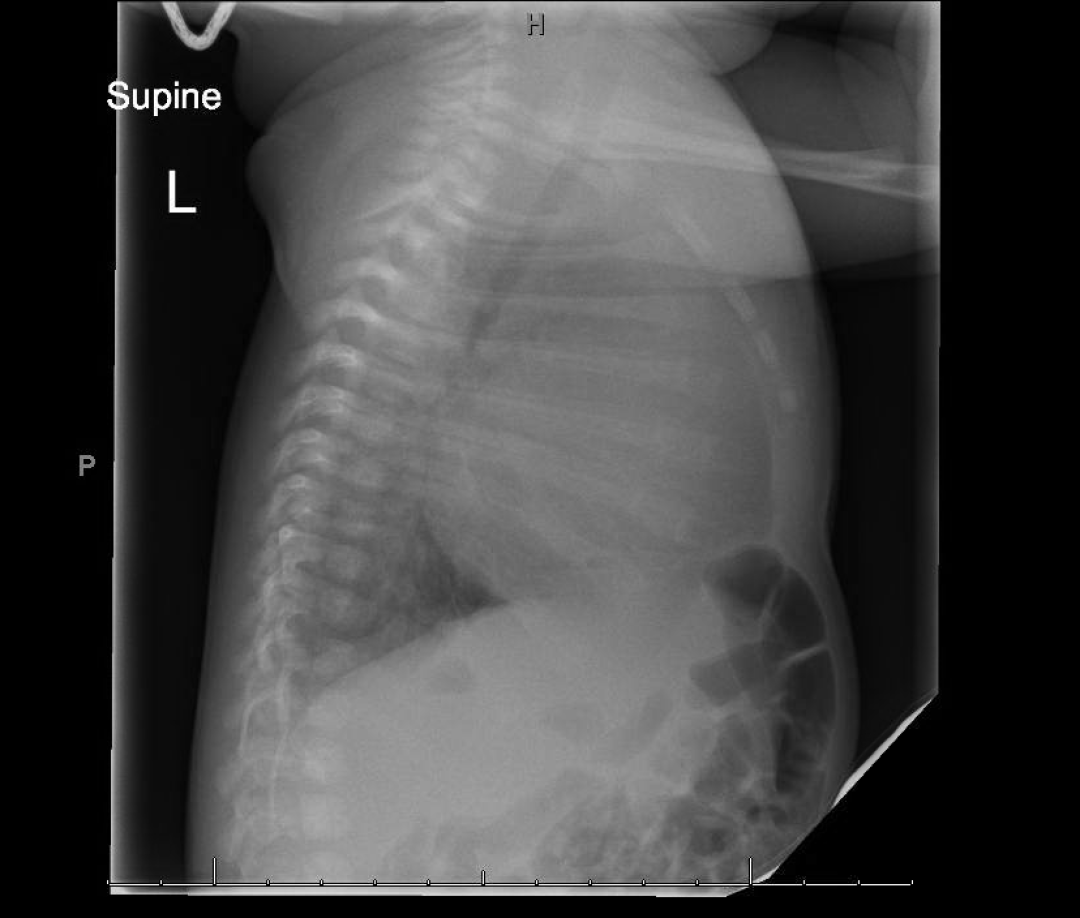

Initially a CXR was obtained:

There was much debate as to whether or not there was cardiomegaly. Mild interstitial opacities were noted.